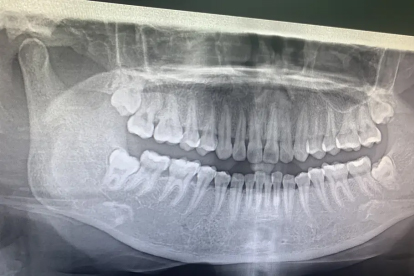

若出现持续剧烈疼痛、张口受限、发热等严重症状,需立即就诊口腔外科。医生可能进行局部切开引流、冠周冲洗等处理,必要时拍摄口腔全景片评估智齿位置。对于反复发炎的阻生智齿,待急性炎症控制后建议手术拔除。